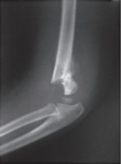

5~6岁以下的儿童,有明显摔伤等外伤史,肘关节局部屈伸功能,肿胀疼痛明显,肘后三角关系存在,肘部处于半屈位,肘窝饱满。正侧位X线检查可见伸直型肱骨髁上骨折的骨折线位于肱骨下段鹰嘴窝水平或其上方,骨折的方向为前下至后上,骨折向前成角,远折端向后移位。屈曲型肱骨髁上骨折的骨折线可为横断,骨折向后成角,远折端向前移位。肱骨髁上骨折经典的分型即Gartland分型:Ⅰ骨折无骨折移位;Ⅱ型骨折有完整的后铰链;Ⅲ型骨折完全移位;Ⅳ型骨折前后骨膜铰链的完整性完全丧失,肘关节屈伸时均不稳定。